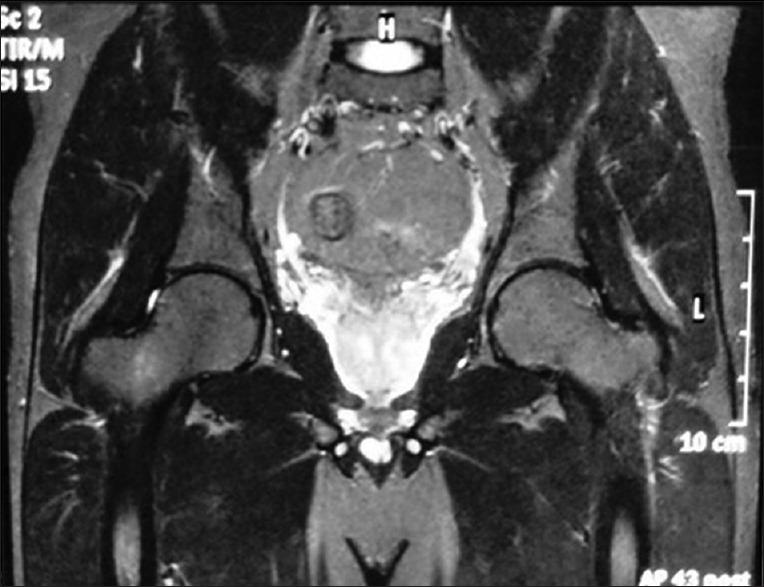

All the patients were treated conservatively by nonweight bearing mobilization, anti-inflammatory drugs, bisphosphonates, calcium, and Vitamin D supplements. None of our patients had any symptoms after 6 months of conservative management. The disease did not progress, and there was no evidence of hip joint involvement in any of the cases. Plain radiographs were not diagnostic in the early detection of TOH. Magnetic resonance imaging was found to be highly specific and sensitive in diagnosing TOH. The clinical condition of TOH is characterized by its acute onset of hip pain in middle-aged people, and its symptoms are out of proportion to the radiological findings.

所有患者均通过非负重活动、抗炎药物、双膦酸盐、钙剂和维生素D补充剂进行保守治疗。保守治疗6个月后,所有患者均无任何症状。疾病未进展,所有病例均无髋关节受累的证据。X线平片在TOH早期检测中无诊断价值。磁共振成像在诊断TOH方面具有高度特异性和敏感性。TOH的临床特征为中年患者急性髋部疼痛,其症状与影像学表现不成比例。